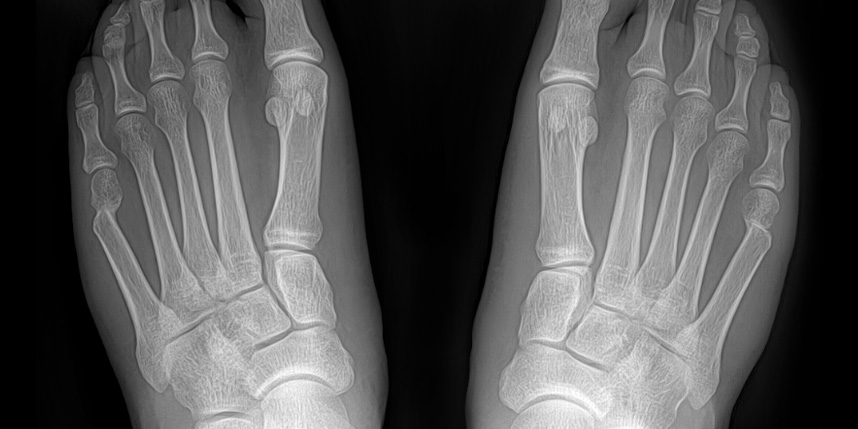

개방형 원위 절골술의 경우 절골 방법은 SERI 와 비슷하지만

조금 더 안정적이고 절개가 크지 않으면서 연부조직의 처리가 같이 가능하기 때문에 필요한 경우 적용할 수 있습니다.